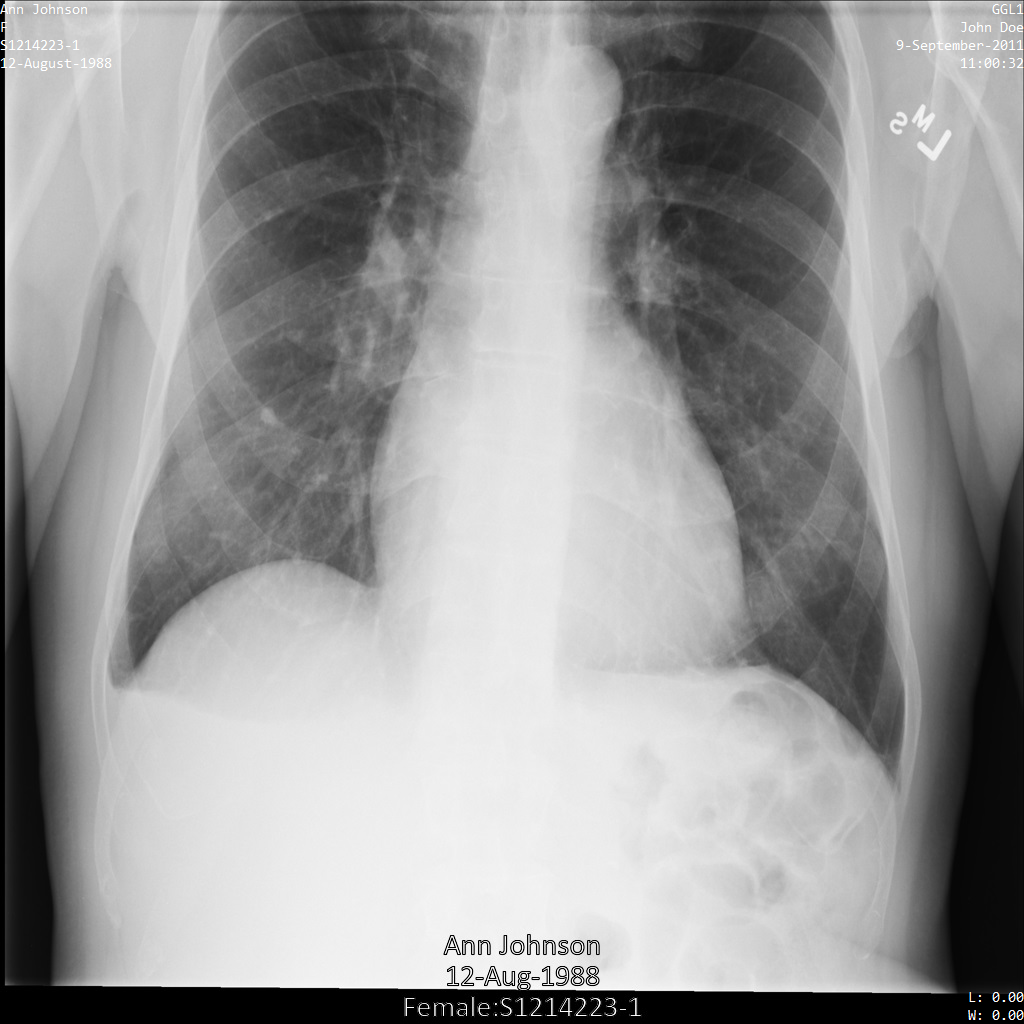

Imagen de muestra

Algunas muestras de esta página contienen el resultado de la imagen anonimizada. En cada ejemplo se usa la siguiente imagen original como entrada. Puedes comparar la imagen de salida de cada operación de anonimización con la imagen original para ver los efectos de la operación: